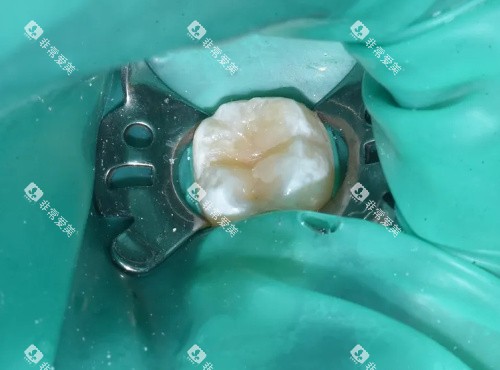

如果是后牙局部磨损,嵌体修复就是一个很合适的方法。

嵌体是用金属或陶瓷材料制作成与牙齿缺损部位相匹配的修复体,然后嵌入到牙齿的缺损部位。

嵌体修复的优点在于它的更准一些度很高。

医生会根据牙齿的缺损情况,正确地制作嵌体,嵌入后能非常好地修养牙齿的外形和咬合功能。

而且嵌体的耐磨性和强度都比较好,使用寿命也比较长。

价格方面,嵌体修复的费用和全冠修复差不多,具体也得看使用的材料。

金属嵌体相对便宜一些,陶瓷嵌体的美观度更好,价格也会高一些。